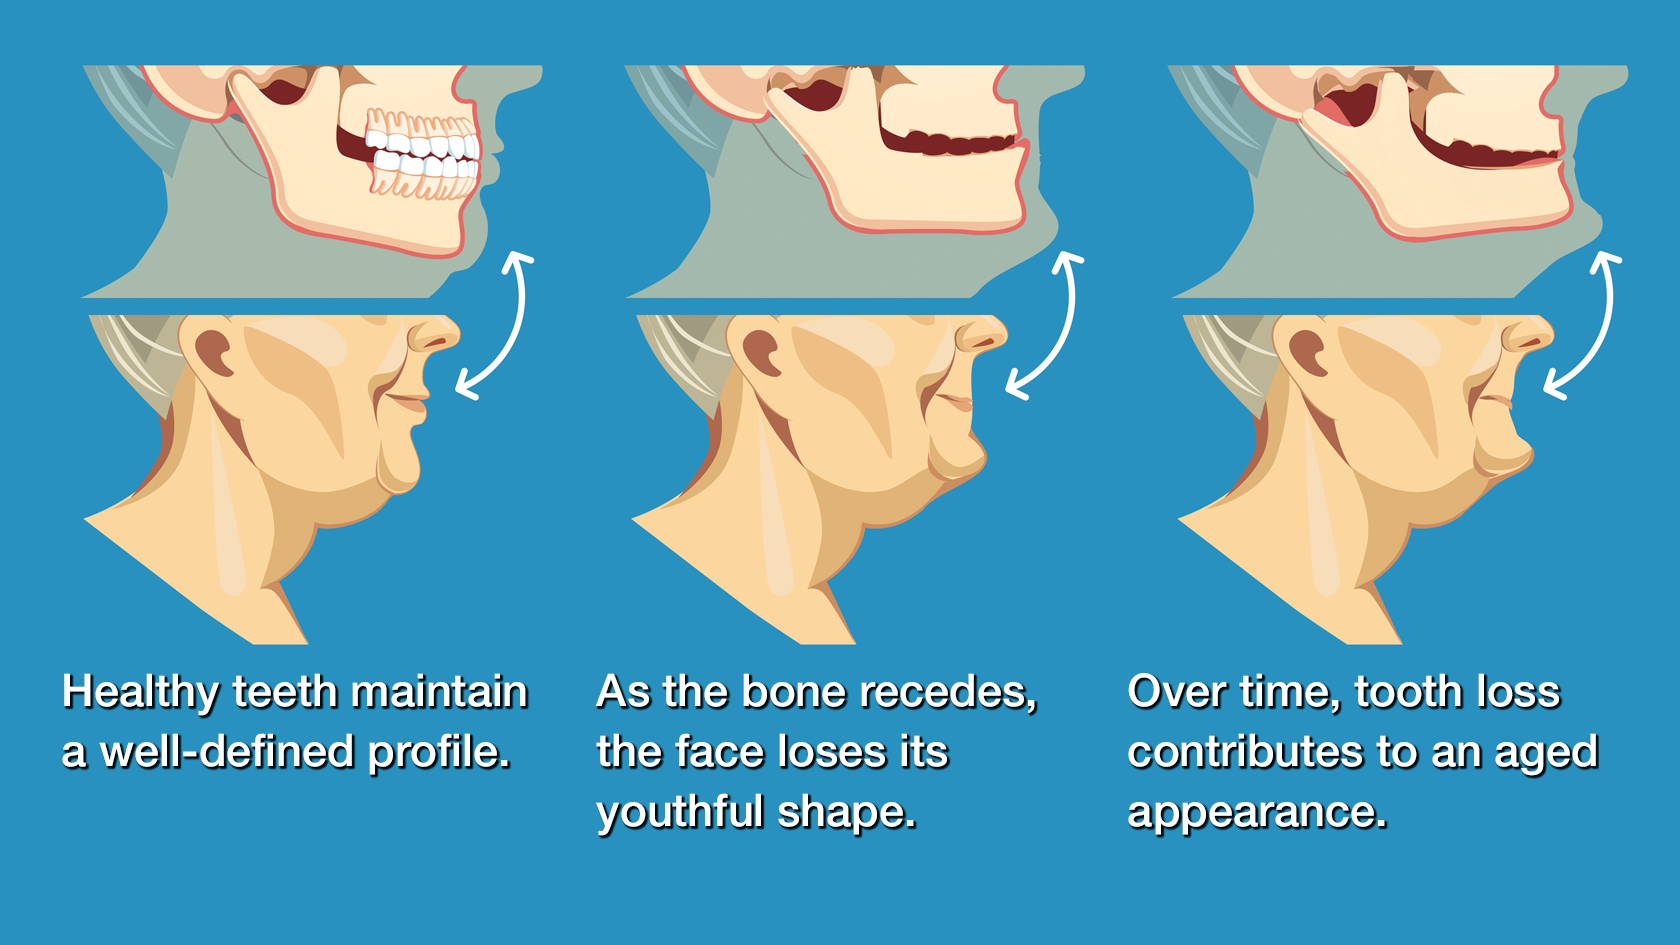

Tooth Loss

- Jawbone Atrophy